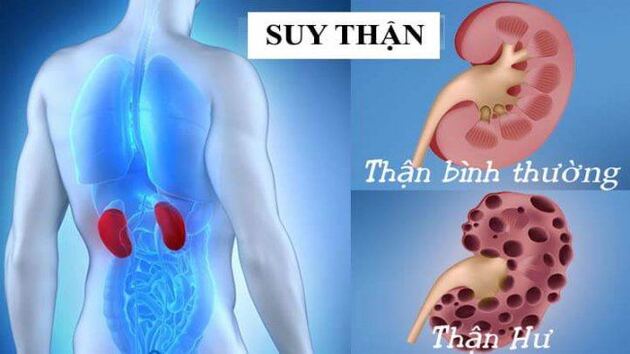

Bác sĩ chia sẽ các dấu hiện bệnh suy thận

Suy thận là tình trạng thận không còn hoạt động hiệu quả nữa. Bình thường thận thực hiện một công việc quan trọng trong cơ thể bằng cách loại bỏ chất thải và chất lỏng dư thừa. Bệnh suy thận gây tử vong nếu không được điều trị thích hợp. Suy thận đôi khi chỉ ...